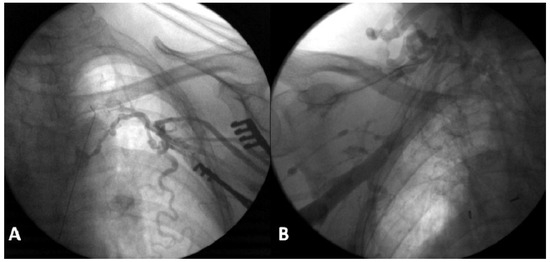

Pacemaker implantation via the femoral vein has been described since the 1980s. This technique is not very well known, but may be useful in some circumstances. We describe a case of a patient with sinus dysfunction without superior venous access, in...